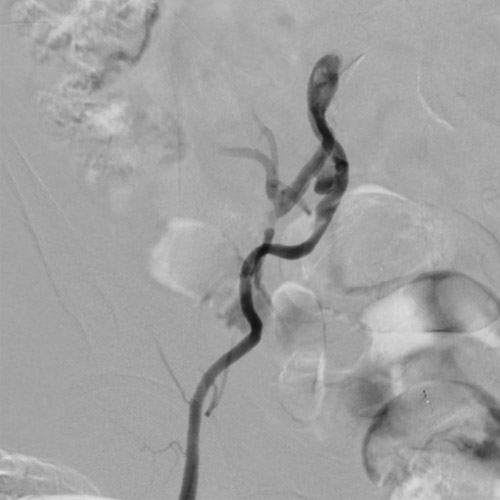

EIAの動脈瘤部にはカバードステントを留置することにした。6gワイヤー(0.014“)のままカバードステントのデリバリーを試みるが、バックアップが弱くEIAまで到達できなかった。6gワイヤーからサポート性の高い0.018ワイヤーに交換したが、ワイヤーが末梢まで到達できなかった。ラジフォーカスガイドワイヤーMスティッフ(0.035”)に交換することでサポート性を更に高めてデリバリーをし、カバードステントがIIA入口を塞がないように出来るだけ奥までデリバリーして留置した(図5)(図6)。

その際、R2P SlenGuideと止血弁の組合せでは、R2P SlenGuide先端からカバードステント本体部分を突出させるにはほとんど余裕がなかった。ガイドカテ全長とステントグラフト長の組み合わせには注意が必要と考えられた。

CIAにR2P Misago 9-40mmを留置。ステントproximalはCIA入口部ジャストに合わせたが、R2P Misagoはリリース時に位置ずれしにくく狙った位置に留置できた(図7)。